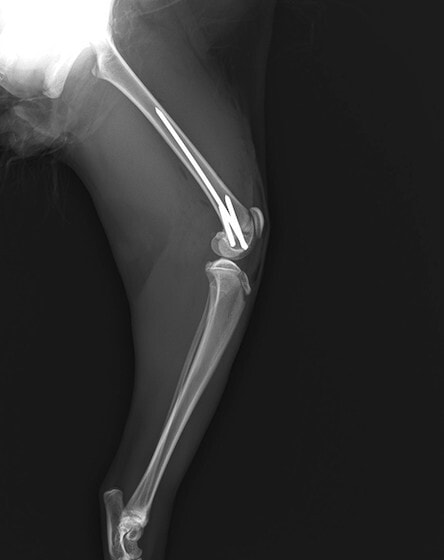

症例3:キルシュナーワイヤーのピンニングによる整復

ペルシャ猫 11ヶ月齢 雄

他院にて左大腿骨遠位の成長板骨折(salter-harrisⅠ型)が認められており、治療相談を目的として来院。当院にて、キルシュナーワイヤーを用いたピンニングにより骨折部位の整復を行いました。術後の経過は良好で、現在も経過観察中です。

術前レントゲン

術後レントゲン